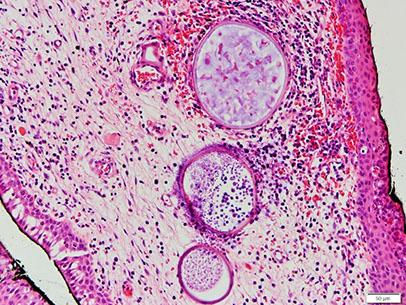

Rhinosporidiosis

most likely a fungal infx of URT 2/2 Rhinosporidium seeberi, seen in livestock and transmitted in water and dust

- M>F, endemic to South Asia, and South America

- sporadic in USA

- causes nasal obstruction

Micro: large (up to 300 um) sporangia in submucosa c lots of endospores

- may have thick sq mucosal epithelium, inc chronic inflam, not commonly granulomatous

DDx: coccidioidomycosis (sporangia are smaller), cylindrical cell papilloma

Tx: excision (no abx available for this organism)